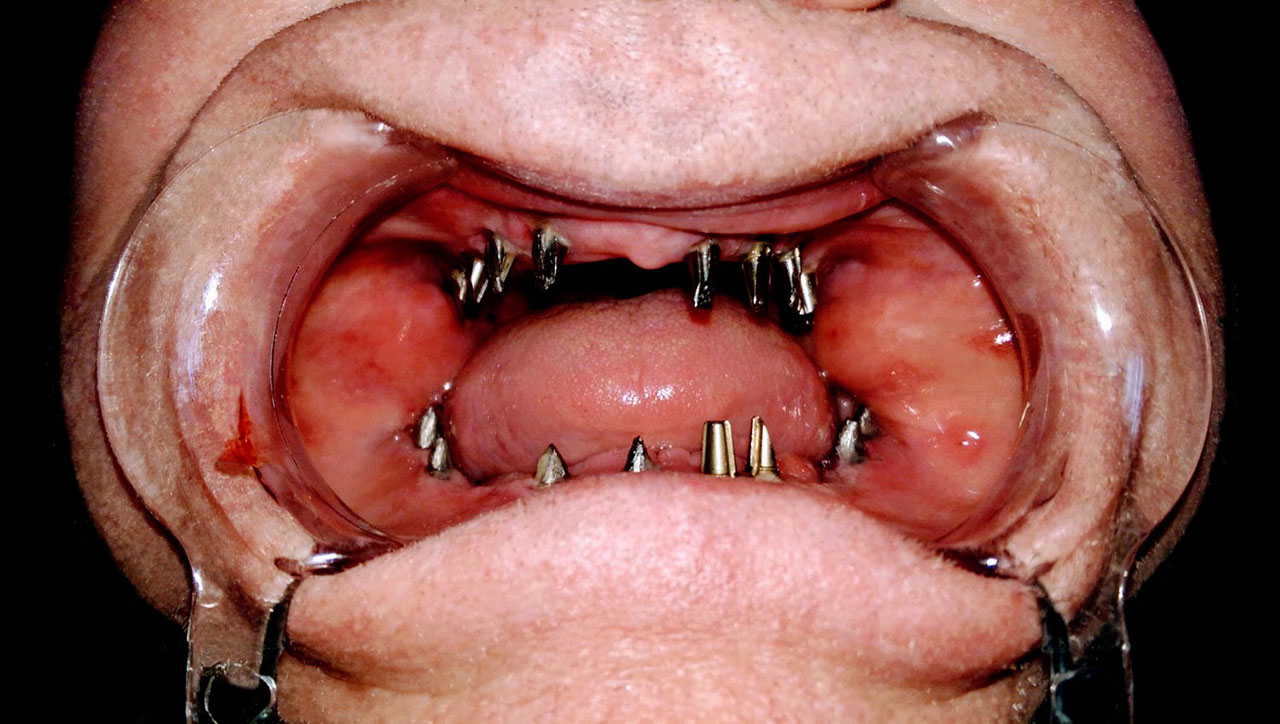

Esetbemutató

• esettanulmany-01

Implantáció előtt, gyulladt, törött fogak.

• esettanulmany-03

Imlantáció után,bal oldalon már a végleges hidakkal, jobb oldalon még csak az implantátumok.